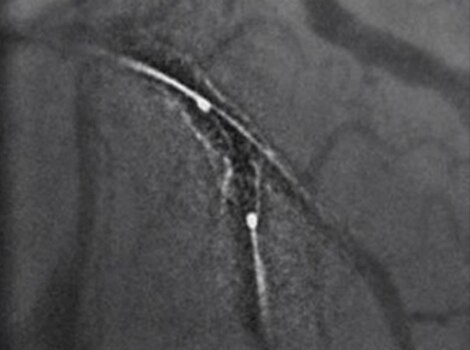

Intervention(介入)

对于送往导管室进行血运重建的患者,我们会尝试快速进入罪犯血管并完成进一步的冠状动脉评估。快速干预可以帮助减少从首次医疗接触开始的再灌注时间。

Innova IGS 5 或 Discovery IGS 7

业界对探测量子效率(DQE)的最高评级之一,可有助于减少使用造影剂和剂量。12 了解更多信息

PCI ASSIST13

帮助规划、评估和指导介入手术,在移动解剖学中可视性提高达 85%。了解更多信息

成功的狭窄新病变 PCI 包括对罪犯病变的规划、指导和评估,以及对冠状动脉其余部分的评估。

Innova IGS 55

业界对探测量子效率(DQE)的最高评级之一,可有助于减少使用造影剂和剂量。

PCI ASSIST6

帮助规划、评估和指导介入手术,在移动解剖学中可视性提高达 85%。